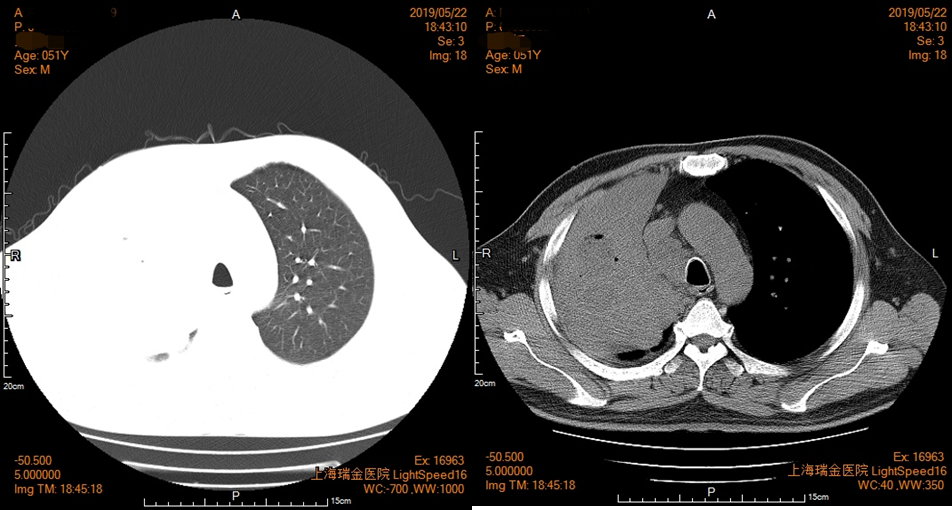

2019年5月22日入院评估治疗疗效,胸部CT显示右肺门及上叶占位伴右肺上叶阻塞性肺不张,较前片(4月29日)进展,纵隔淋巴结肿大,两肺下叶评估进展,间断高热伴感染(图3)。

图3 患者胸部CT影像资料(2019年5月22日)